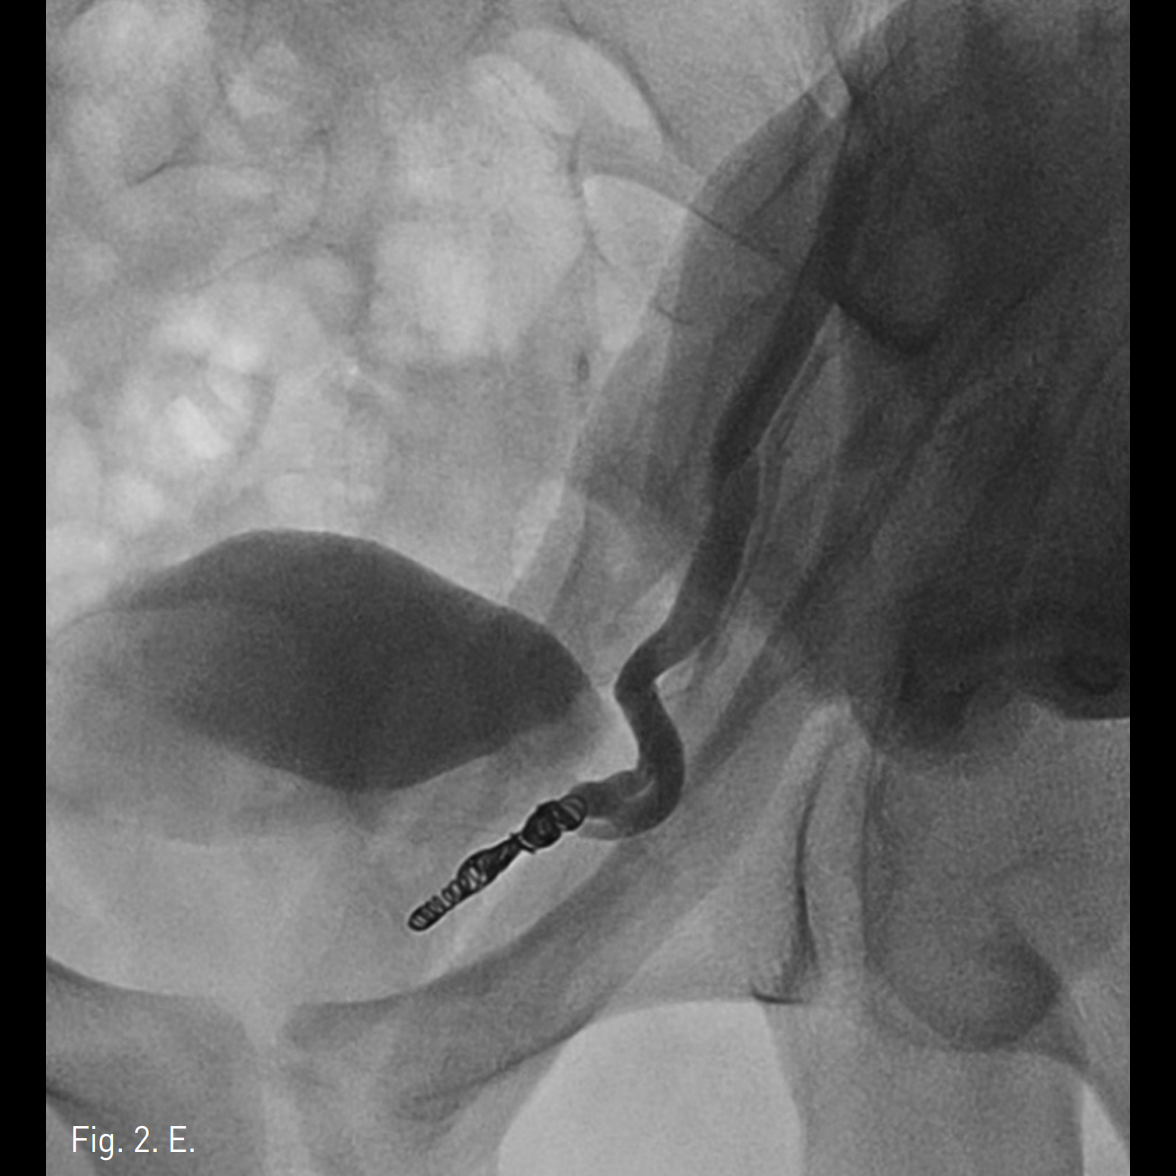

신체검진에서 좌측 고환 상부에 grade ⅡI의 정계정맥류가 있으며 좌측 서혜부에 수술흉터가 있음. 고환 도플러초음파에서 좌측 고환에 pampiniform plexus가 확장되어 있으며 Valsalva maneuver에서 더 두드러지는 소견을 보이고 최대 직경 약 4.5mm로 측정됨 (Fig. 1).

Fig. 1

Doppler US shows dilated veins within the left pampiniform plexus. The maximal diameter of the vein was about 4.4mm. Dilation became more prominent with Valsal va man euver.